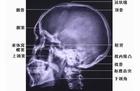

1.頭顱X線正側位相可瞭解骨折範圍、性質及骨碎片的位置、大小,故應常規拍攝。2.顱蓋骨骨折大部分伴有硬膜外血腫,頭顱CT除對顱骨骨折明確診斷外,尚能確定是否伴有顱內血腫,腦水腫以及深部結構是否損傷。為手術治療提供了準確依據,故疑有硬膜外血腫的應行頭部CT檢查。3.腦電圖檢查多在損傷晚期、傷口癒合後進行,對傷後癲癇的定位診斷有重要意義。